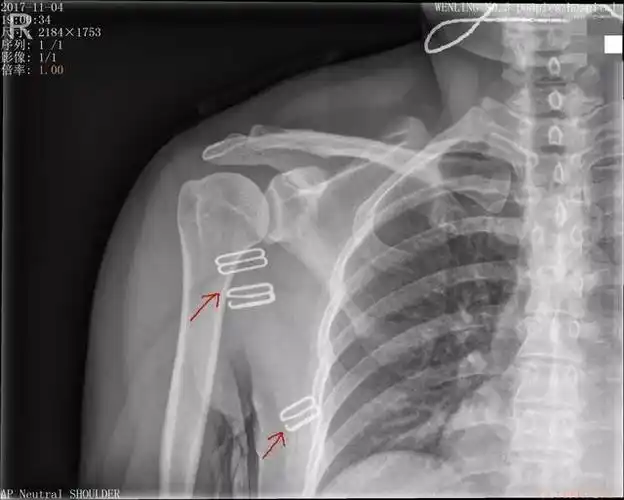

中年女性,发现右肩关节占位2天.有特征,有细节---(有结果)

肩关节x线检查特殊体位